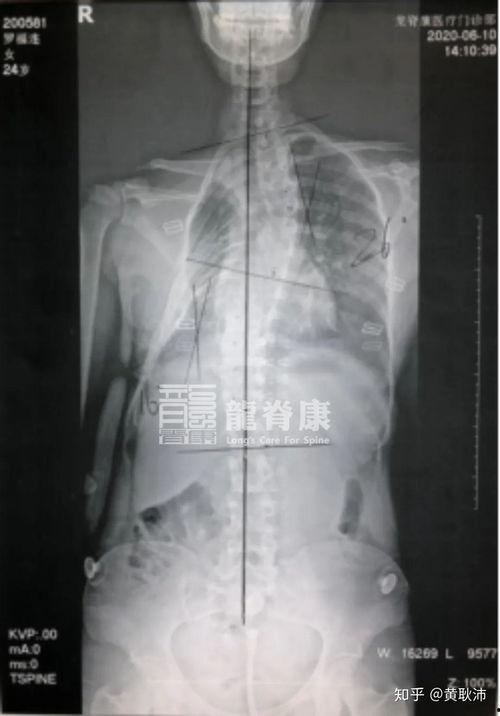

3. 脊柱侧弯:脊柱向一侧弯曲,严重时可能会影响呼吸和心脏功能。

1. 诊断:医生会通过询问病史、体格检查、影像学检查(如X光、CT等)来诊断胸廓畸形。